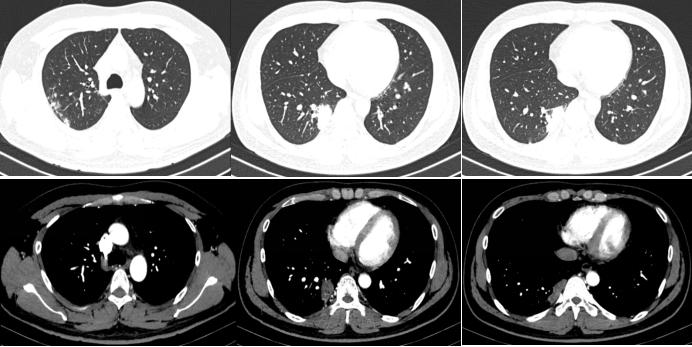

我院胸部CT(2018-6-6)

胸部CT的变化情况:

本病例的疑问: 为什么患者在血隐球菌抗原下降的过程中,出现临床症状和影像学改善不理想?